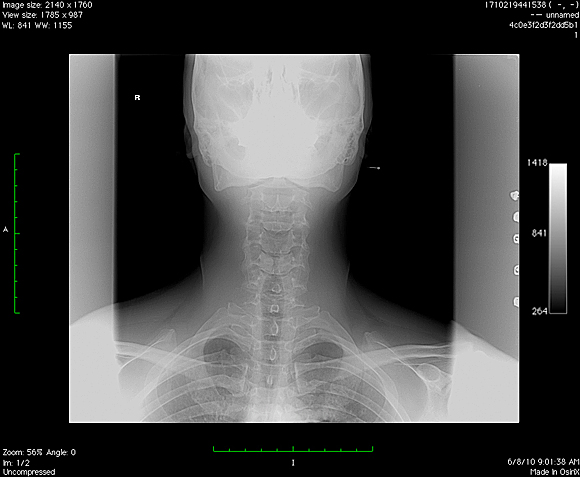

Ma tot gandesc de ceva timp la o noua schimbare pentru fotografiile de la biografie si m-am decis, intr-un fel anume, diferit de imaginile clasice, RADIOGRAFII . Radiografia este ruda cu fotografia, dex-ul spune ca ea reprezinta fotografierea interiorului unui corp opac, in special a unor regiuni din interiorul corpului omenesc sau animal, cu ajutorul razelor x, practic, conform dex-ului, va prezint mai mult… A patra din pacate nu a iesit cum imi inchipuiam aparatul de fotografiat fiind oarecum estompat din cauza unghiului prost ales, din pacate nu am putut s-o refac deoarece 3 radiografii/zi inseamna o cantitate suficient de mare de radiatii.

p.s. Am completat cu o panoramica dentara, cu un RMN la coloana si cu doua radiografii cervicale. Seria continua !